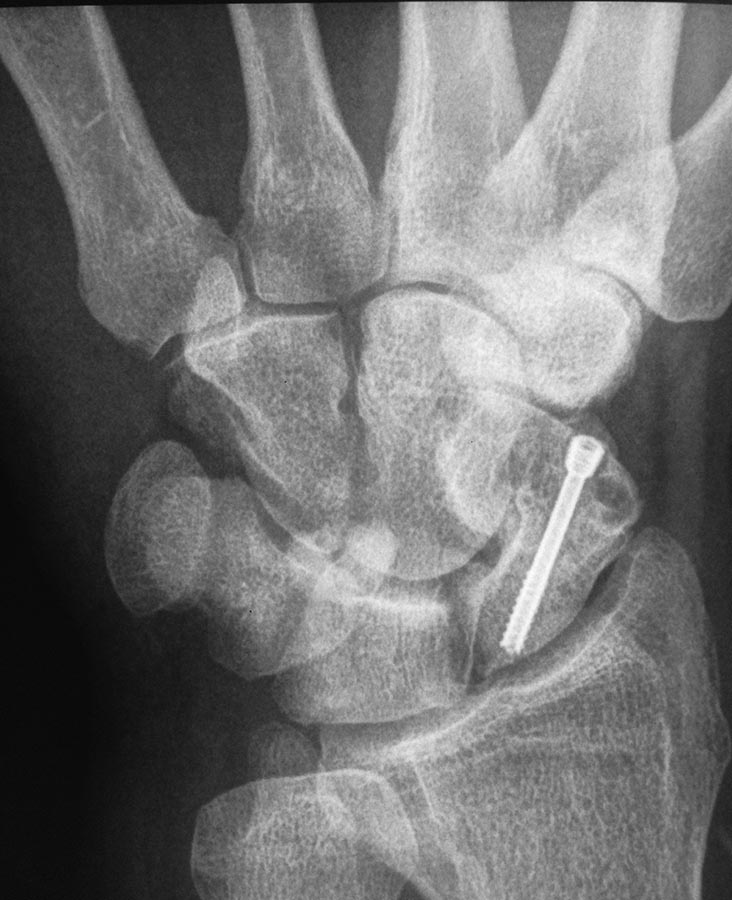

Здравствуйте. Мужчина 30 лет. Травма около 5ти лет назад, МОС винтом, в

данное время в проекции ладьевидной кости болей нет, осевая нагрузка на

1ю пястную кость безболезненная, боли беспокоят при пальпации в проекции

трехгранной кости и движениях в лучезапястном суставе (при пассивных и

активных движениях возникают острые боли, так же в проекции

трехгранной кости). На МРТ отмечаются проблемы в этой зоне. Со слов